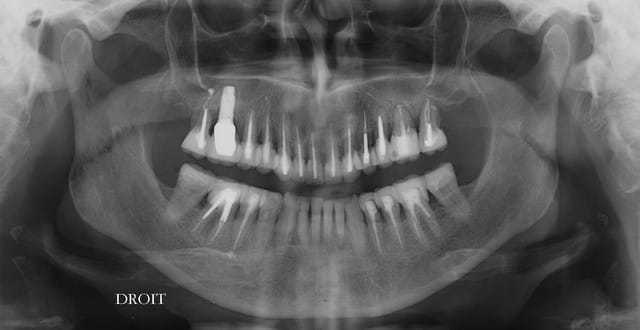

petit panoramique de contrôle, ce n'est pas gagné, mais ça semble aller dans le bon sens.

32?

Ce matin pose de 8 ceramoceram (emax press) à la mandibule et pano de contrôle.

non,l'implant n'est pas "dans le sinus", mais dans une greffe, qui est elle même dans le sinus (comblement) rien d'anormal, pour cet implant.